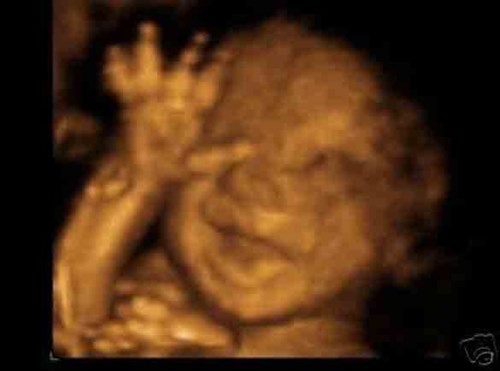

Bé yêu biết cười. Rất nhiều mẹ đã bắt gặp khoảnh khắc bé cười toe toét qua hình ảnh siêu âm đấy, điều này là hoàn toàn bình thường và đây thực sự là món quà quý giá với bất cứ người mẹ, người cha nào.